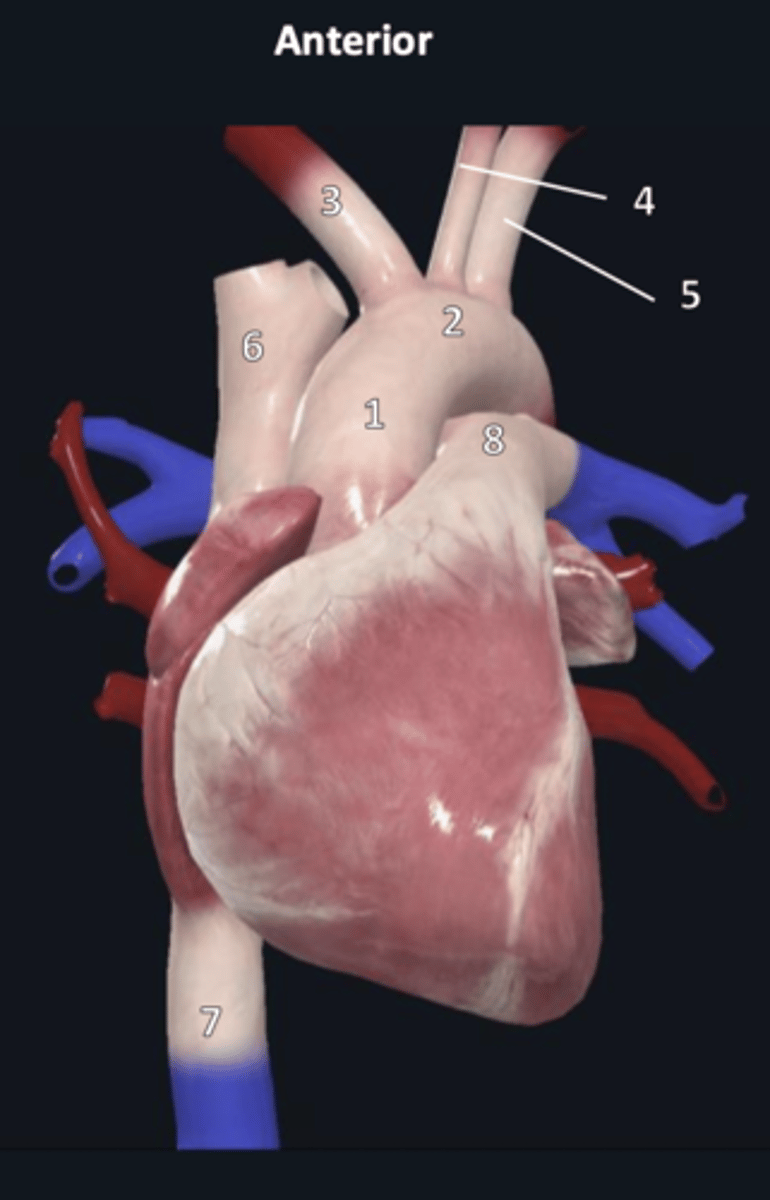

ascending aorta

1

aortic arch

2

brachiocephalic trunk

3

left common carotid artery

4

left subclavian artery

5

superior vena cava

6

inferior vena cava

7

pulmonary trunk

8